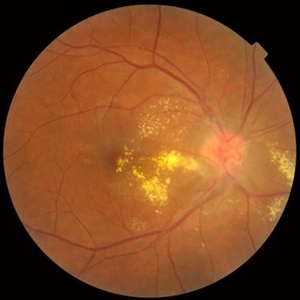

Behcet's Disease Behcet's DiseaseMar 13 2013 by Hamid Ahmadieh, MD Early phase FA of the right eye of a 23-year-old man with retinal vasculitis and branch retinal vein occlusion (BRVO) due to Behcet's disease . Photographer: Solmaz Shahmohammad, Negah Eye Center, Tehran Imaging device: Heidelberg Spectralis Condition/keywords: branch retinal vein occlusion (BRVO), retinal vasculitis

Behcet's Disease Behcet's DiseaseMar 13 2013 by Hamid Ahmadieh, MD Mid phase FA of the right eye of a 23-year-old man with retinal vasculitis and branch retinal vein occlusion (BRVO) due to Behcet's disease . Photographer: Solmaz Shahmohammad, Negah Eye Center, Tehran Imaging device: Heidelberg Spectralis Condition/keywords: branch retinal vein occlusion (BRVO), retinal vasculitis